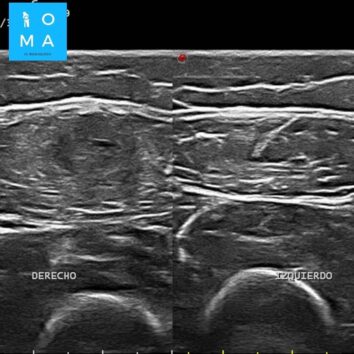

🔹Cambios inflamatorios asociado a edema y banda líquida que rodea a la unión miotendinosa central del sector medio del músculo recto anterior del cuádriceps derecho, de 10 mm de extensión, evocador de desgarro de la unión miotendinosa grado II.

🔹En un segundo tiempo se realiza ecografía dirigida, confirmando los hallazgos a nivel del tendón central del músculo recto

anterior del cuádriceps derecho, presentando desgarro grado II, asociado a un